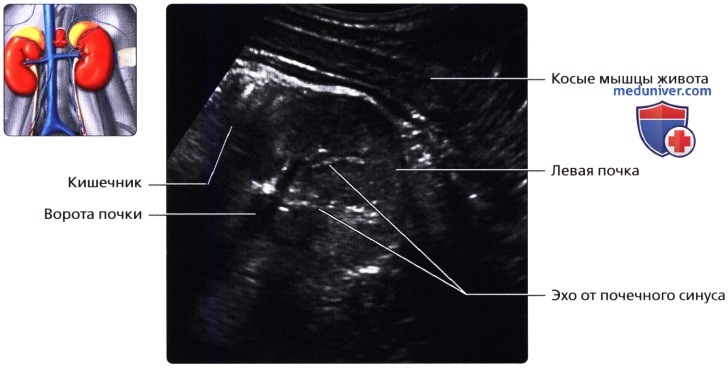

Специалист накладывает над поясничной областью специальный гель, обеспечивающий оптимальный контакт датчика с поверхностью кожи и отсутствие воздушной прослойки, что усиливает ультразвуковой сигнал.

Для полноценного мониторинга органов обследуемый должен сделать серию глубоких вдохов. Акустический ответ, возникающий при прохождении ультразвуком мягких тканей, передается датчиком в УЗИ-аппарат, где визуализируется на мониторе в виде точного изображения органа.

В процессе наблюдения врач может изменять масштаб изображения, увеличивая интересующие фрагменты. Во время диагностики фиксируются основные морфологические показатели и характеристики обеих почек.

Сначала исследуют почки в продольном направлении (поясничная область), затем изучают поперечные и косые срезы, перемещая датчик на переднюю и боковые поверхности живота. При этом пациента просят поочередно повернуться на правый и левый бок. Такая техника позволяет определить локализацию (месторасположение) почек, их размеры и форму, оценить состояние паренхимы, почечных синусов, чашечек и лоханок.

Для определения подвижности почек и улучшения визуализации органов при каждом изменении положения тела врач просит больного вдохнуть и на несколько секунд задержать дыхание. На вдохе почки опускаются из-под реберной дуги и просматриваются намного лучше. УЗИ почек стоя делают при подозрении на нефроптоз (опущение одной или обеих почек).

Интерпретация результатов исследования выполняется только врачом-сонологом. В заключении специалист указывает количество почек, их анатомическое положение, подвижность, размер и форму, количество и состояние мочеточников, описывает структуру чашечно-лоханочного аппарата и паренхимы почек.

УЗИ почек в норме, если: